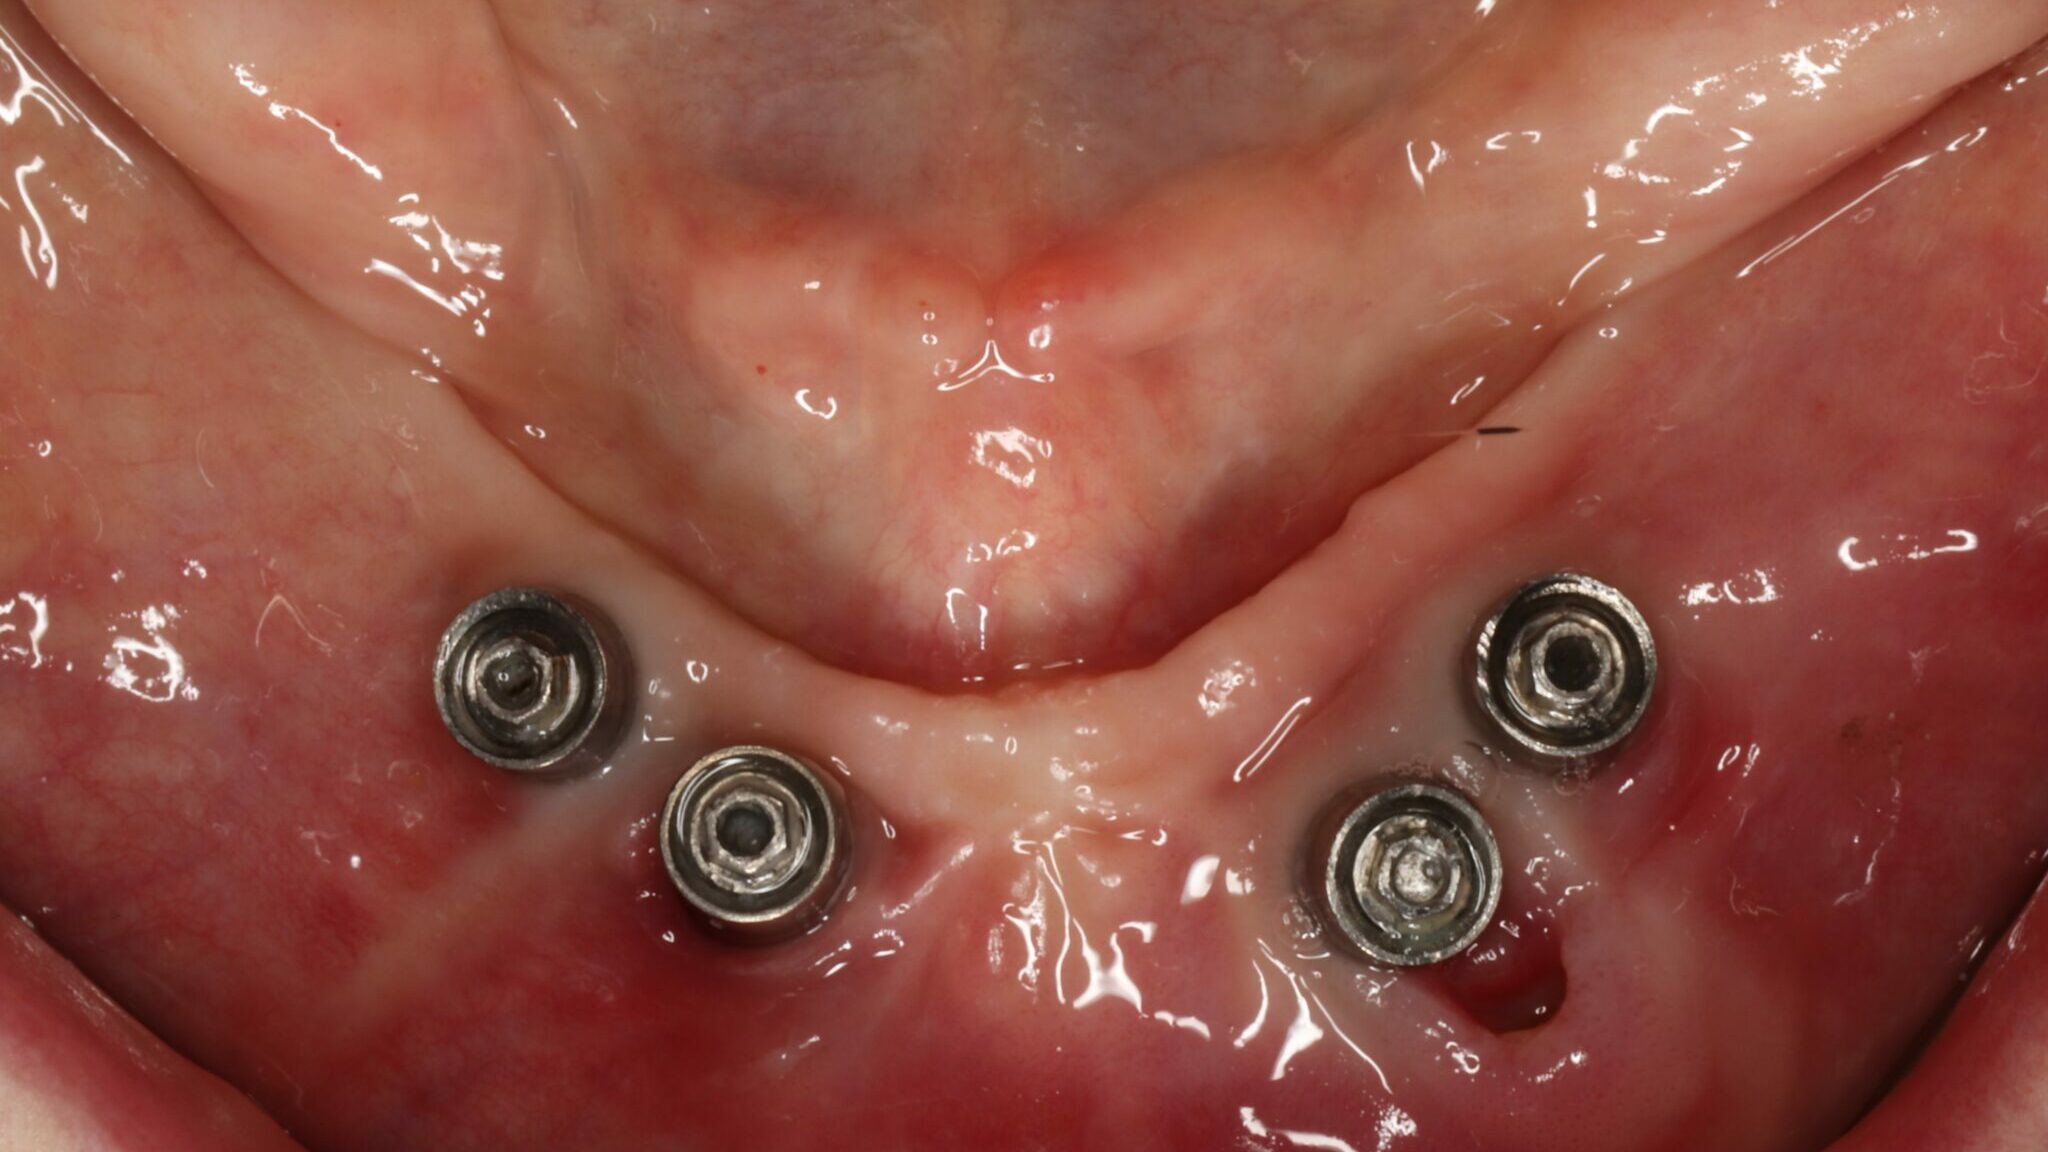

Edentulism in the posterior maxillary region presents a challenging scenario for dental implant rehabilitation due to vertical ridge dimension bone loss and the close proximity to the floor of the maxillary sinus. In addition, alveolar ridge width loss and thinning of mucosa is a common clinical scenario in areas of long term tooth loss. To … Read more